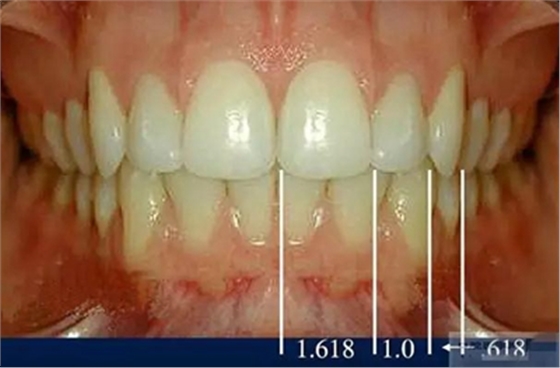

審美序列清單:

1、切牙的位置長度

2.頜學(xué)

3.牙齒寬度

前牙的黃金分割比例

正面觀

側(cè)切牙約為中切牙的60%

尖牙約為側(cè)切牙的60%

4.牙齒比例

中切牙正常/理想的 寬/長百分比約為75%—80%